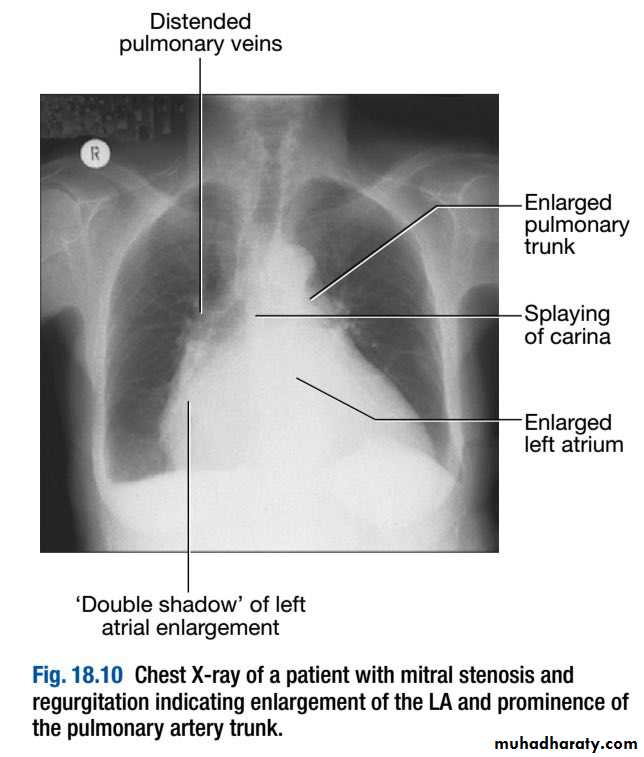

Chest X-ray

This is useful for determining the size and shape of the heart, and the state of the pulmonary blood vessels and lung fields. Most information is given by a postero-anterior (PA) projection taken in full inspiration.Anteroposterior (AP) projections are convenient when patient movement is restricted but result in magnification of the cardiac shadow.

An estimate of overall heart size can be made by comparing the maximum width of the cardiac outline with the maximum internal transverse diameter of the thoracic cavity.

‘Cardiomegaly’ is the term used to describe an enlarged cardiac silhouette where the ‘cardiothoracic ratio’ is > 0.5. It can be caused by chamber dilatation, especially left ventricular dilatation, or by a pericardial effusion.

Dilatation of individual cardiac chambers can be recognised by the characteristic alterations to the cardiac silhouette:

- Left atrial dilatation results in prominence of the left atrial appendage, creating the appearance of a straight left heart border, a double cardiac shadow to the right of the sternum, and widening of the angle of the carina (bifurcation of the trachea) as the left main bronchus is pushed upwards.

-Right atrial enlargement projects from the right heart border towards the right lower lung field.

-Left ventricular dilatation causes prominence of the left heart border and enlargement of the cardiac silhouette. Left ventricular hypertrophy produces rounding of the left heart border.

- Right ventricular dilatation increases heart size, displaces the apex upwards and straightens the left heart border.

The lung fields on the chest X-ray may show congestion and oedema in patients with heart failure , and an increase in pulmonary blood flow (‘pulmonary plethora’) in those with left-to-right shunt. Pleural effusions may also occur in heart failure.